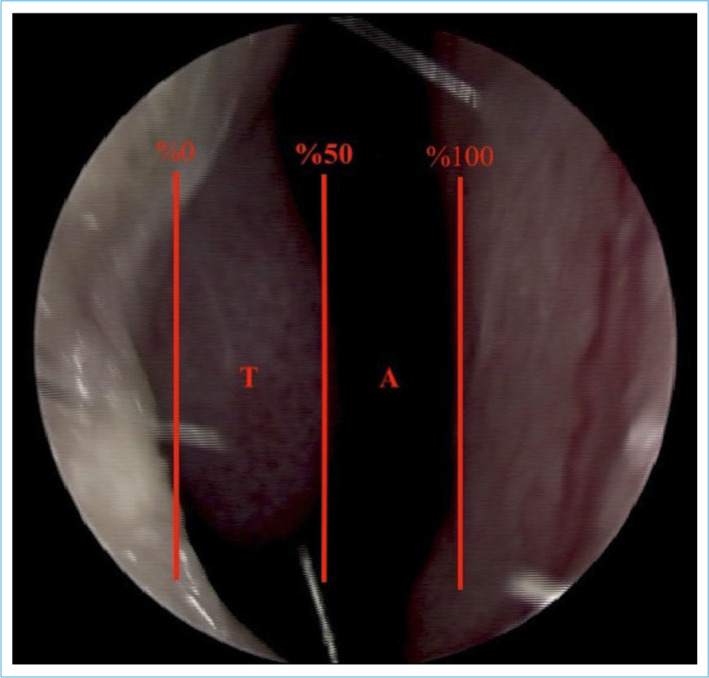

Methods: This case-control study was conducted with patients diagnosed with HTS during dermatologic examination and a control group without HTS. An otolaryngologist evaluated the presence and severity of inferior turbinate hypertrophy by anterior rhinoscopy.